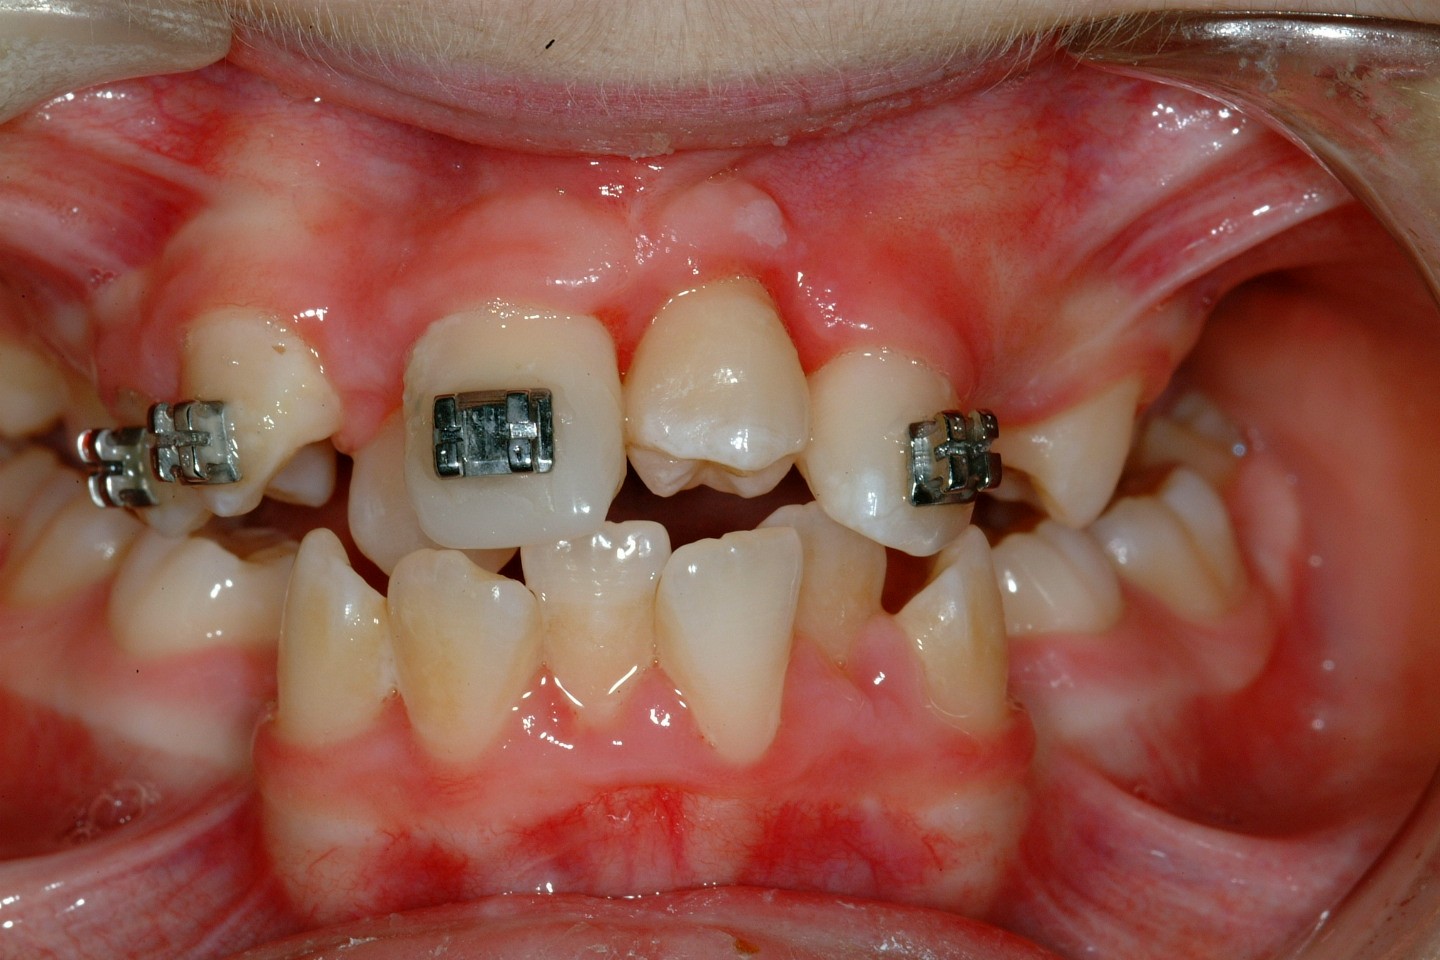

For satisfactory results to be achieved by surgical exposure and alignment of ectopic canines, complex fixed-appliances treatment for sometimes in excess of two years is required. Such appliances may include the need for dual-arch fixed appliances to allow for the use of interarch elastics and to allow arch co-ordination.

Before surgery is undertaken a decision has to be made between open or closed eruption. The aim of any exposure is to uncover enough of the crown either to place an attachment or prevent recovering of the crown during the healing phase. The most important principle of surgery is to ensure the tooth will erupt through keratinized mucosa. If this does not happen, which can occur with buccally placed canines, then the post-treatment periodontal condition will be compromised. This can obviously affect gingival aesthetics and health.

Closed eruption uses an attachment secured to the tooth to apply orthodontic traction and is useful in the treatment of markedly ectopic teeth where it would be difficult to undertake an adequate open exposure. It is often used when the canine is palatally positioned. It can be used for the treatment of buccal canines but the results can be disappointing if the attachment herniates through the thin buccal gingivae. To avoid this, the attachment should be placed either on the tip of the tooth or palatally. This is sometimes not possible because the crown position increases the risk of either excessive bone removal or iatrogenic damage to adjacent structures. It is, however, useful in the treatment of buccal canines if the crown overlies an adjacent tooth and it would be difficult to undertake an apically repositioned flap.